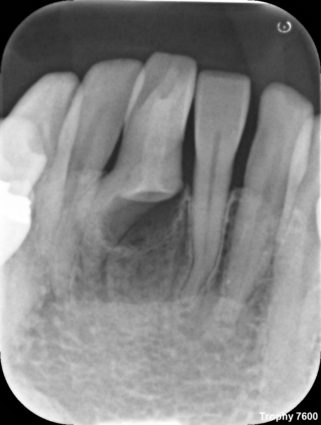

「陥入歯」とは、歯の頭の部分の表層のエナメル質と内部の象牙質が神経のお部屋の中(歯髄腔)にさまざまな程度で陥入している形態異常の歯のことです。少し難しい説明になってしまいましたが、簡単に言うと、歯が作られる過程で陥入することによって形態異常を起こしてしまった歯のことです。歯の中にもう一つ歯ができているように見えることから「歯内歯」と言われたこともありましたが、現在では歯の発生の概念から、歯の外側のエナメル質が内側の象牙質に折り込まれてデッドスペースを形成していると考えられ「陥入歯」として統一されています。

1957年にOehlersは「陥入歯」を以下3つタイプに分類し、現在もこの分類が広く用いられています。従来のOehlersの分類では、歯軸方向への陥入の程度によって3つに分けられていましたが、タイプⅢにおいては、歯根側面に貫通するもの(Ⅲ-a)、根尖に貫通するもの(Ⅲ-b)の2つに分けられ、近年では4つの分類として用いられることが多くなりました。

TypeⅠ:陥入が歯冠部にとどまり、セメントエナメル境(CEJ)を越えないもの。

TypeⅡ:陥入がCEJを越えて歯髄腔内におよぶが、歯周組織との交通がなく、根管内にとどまるもの。

TypeⅢ:陥入が側方の歯周組織(Ⅲ-a)または根尖(Ⅲ-b)に貫通しているもの

Ridellらの文献では、TypeⅠが79%、TypeⅡが15%、TypeⅢが5%と報告されています(※2)。また、好発部位は上顎前歯部と言われています。

普段の臨床では、非常に稀なケースであまりお目にかかることはありませんが、遭遇した際にはCBCTを活用するなど「陥入歯」の構造を把握した上で治療を進めていく必要があると感じました。